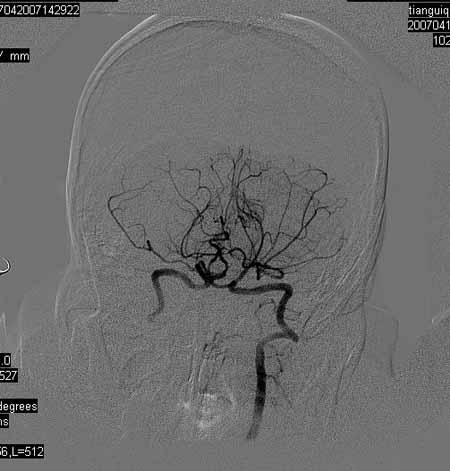

标题: DSA0093:脑血管造影

女,63岁,左侧额、枕叶脑梗塞。

右肾动脉及左颈内动脉起始部狭窄(考虑动脉硬化引起的),大脑中动脉分支减少.